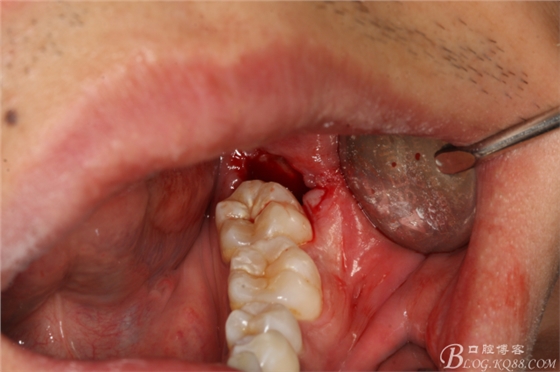

圖5.高速渦輪鉆舌側(cè)潛掘法橫斷牙冠

圖6.舌側(cè)潛掘法完成